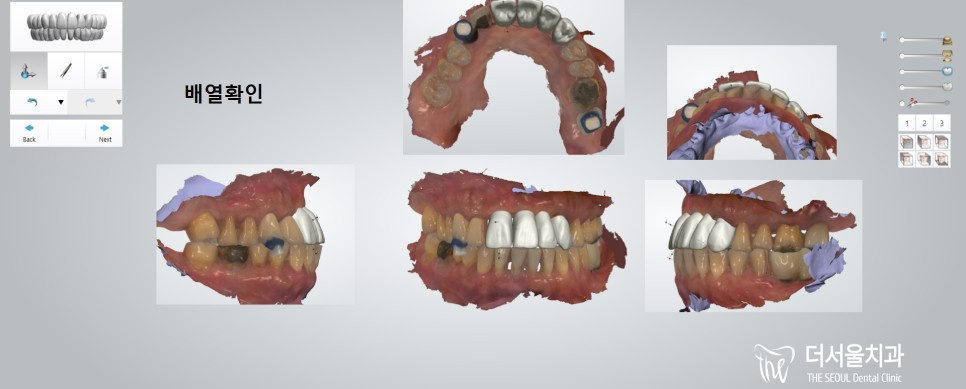

더서울은 환자의 안모, 분위기, 성별 등을 고려해서

최대한 자연스러운 보철을 만들고 있는데요.

특히나 이분은 앞니임플란트 라서

심미성이 더 중요할 수 밖에 없죠.

그리고 약간의 비대칭을 갖고 있었기 때문에

보철 제작 과정에서 배열 및 형태 재현을

좀 더 신경쓰기로 했습니다.